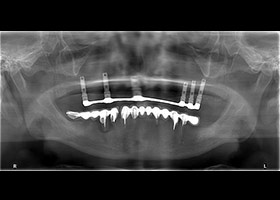

1.病患最初全口X光片。

15.治療完成之全口X光片。